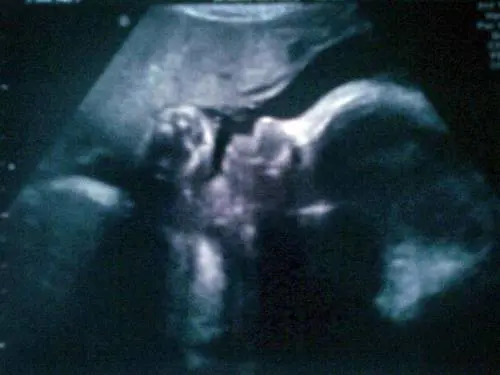

Lo psichiatra Bernardo Carpiniello: "Impossibile negare la realtà della gravidanza per nove mesi"